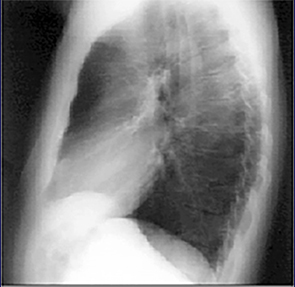

PA and Lateral

Click on the Xrays to enlarge them.

Choose the best interpretation of the chest X rays:

Normal with straight back syndrome

Normal

Dilated ascending aorta

Normal with bilateral accessory rib

Calcified coronary arteries